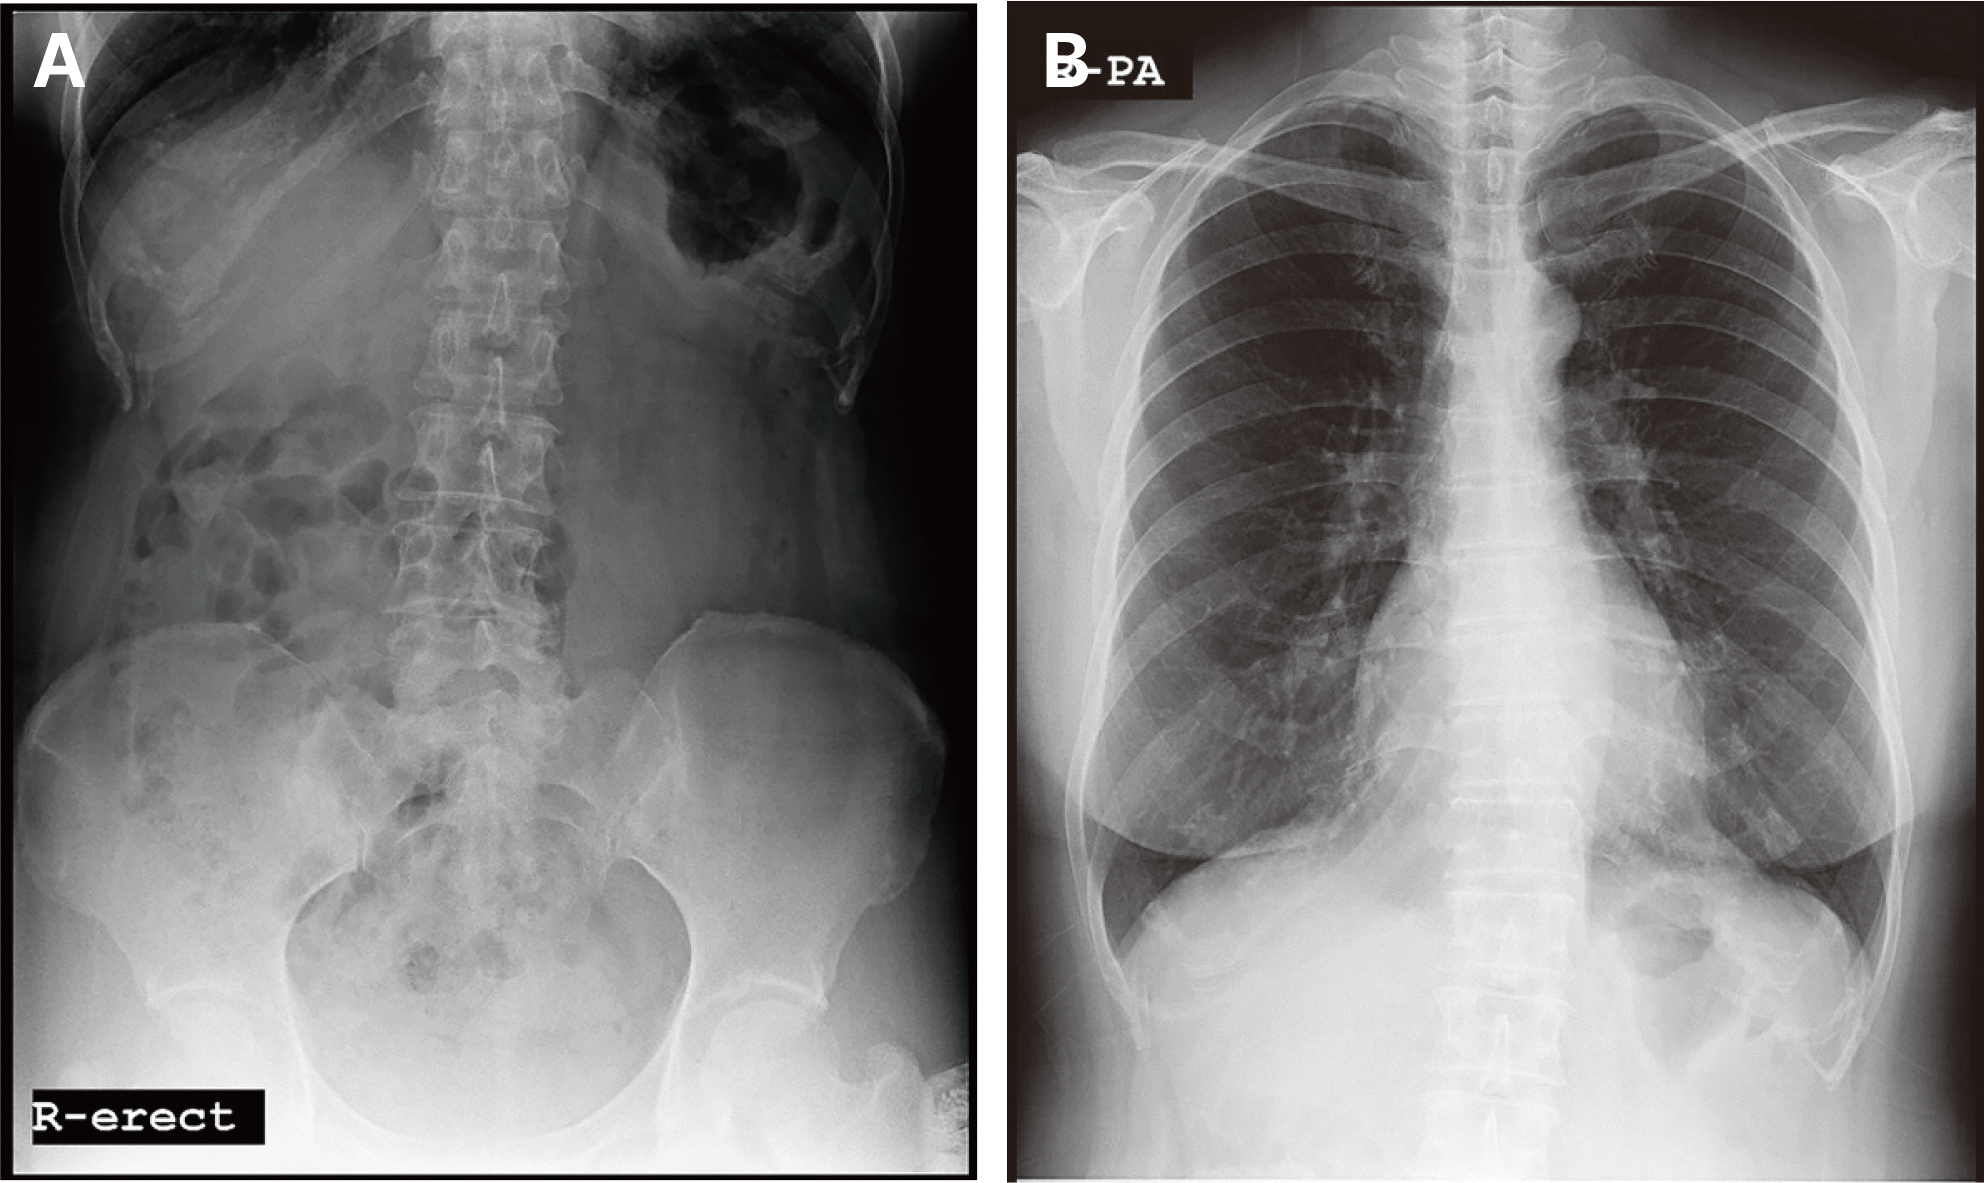

60세 남자 환자로 전체적인 치과치료를 위해 본원에 내원하였다. 환자는 의과적으로 기질성 정신장애를 진단을 받았으며, 거동이 불편하고 보행이 불가능하여 요양병원에서 입원 치료 중이었다. 정신건강의학과에서 환자의 정신장애에 대해 치료상태가 안정된 상태임을 확인한 후, 치과치료를 진행하였다. 파노라마 방사선 사진 및 구강검사에서 상악 우측 제1소구치와 제1대구치, 좌측 제제1, 2소구치, 하악 우측 제1대구치에 잔존 치근이 존재하였으며, 상악 우측 견치와 하악 좌측 견치 및 소구치에서 치아우식증이 관찰되었다(Fig. 1). 환자의 의과적 병력과 치료의 협조도, 구강위생 조절 능력 등을 고려했을 때, 가철성 보철물의 유지와 관리가 어렵다고 판단되어 고정성 보철물로 수복을 계획하였다. 예후가 불량한 상악 우측 견치, 제1소구치, 제1대구치와 좌측 제제1, 2소구치, 하악 좌측 견치, 제1소구치와 우측 1대구치를 발치 한 후, 치아 상실부위에 임플란트 식립을 하였고(Fig. 2), 골유착 기간을 거쳐 최종인상을 채득하였다. 제작한 임플란트 보철물을 장착하던 과정에서 치과의사는 하악 우측 제제1, 2소구치와 제1대구치로 이루어진 3본 지르코니아 보철물이 환자의 구강 내로 떨어뜨렸고, 떨어진 즉시 환자의 두부를 좌측으로 돌려 환자가 보철물을 삼키지 않도록 노력하였으나, 환자가 보철물을 삼키게 되었다. 환자가 보철물을 삼킨 이후 기침이나 구토 반사 등의 특이적 소견을 보이지 않았으며, 호흡상태는 양호하였다. 환자 보호자에게 보철물 장착과정에서 보철물을 구강 내로 떨어뜨렸고, 이후 삼킴이 발생하였음을 설명하였다. 그리고 삼켜진 보철물의 위치 확인을 위하여 인근 내과로 전원 의뢰를 시행하였다. 전원 의뢰된 당일, 내과에서 복부 방사선 사진을 촬영하였고, 판독 결과 보철물이 위장에 위치를 하고 있음을 확인하였다. 24시간 이후 배출될 것으로 예상되어 48시간 후 재촬영이 필요할 것이라는 회신서를 확인하였다(Fig. 3). 2일 후 환자를 내원하도록 하여 추가로 복부 방사선 사진을 촬영하였다. 방사선 사진에서 위장관 내에서 보철물 확인되었다. 환자의 거동이 불편하여 위장관 운동이 저하되어 있는 상태이기 때문에 배출이 지연될 수 있다는 의과적 소견을 회신 받았다(Fig. 4). 8일 후 환자의 복부 방사선 사진을 촬영하였으며, 보철물이 위장관에서 완전히 배출되어 체 내에 있지 않음을 확인하였다(Fig. 5). 이 후 하악 우측 제1, 2소구치와 제1대구치에 새로운 보철물을 제작하여 최종 합착(Rely-X, 3M ESPE, St Paul, USA)을 시행하였다(Fig. 6).